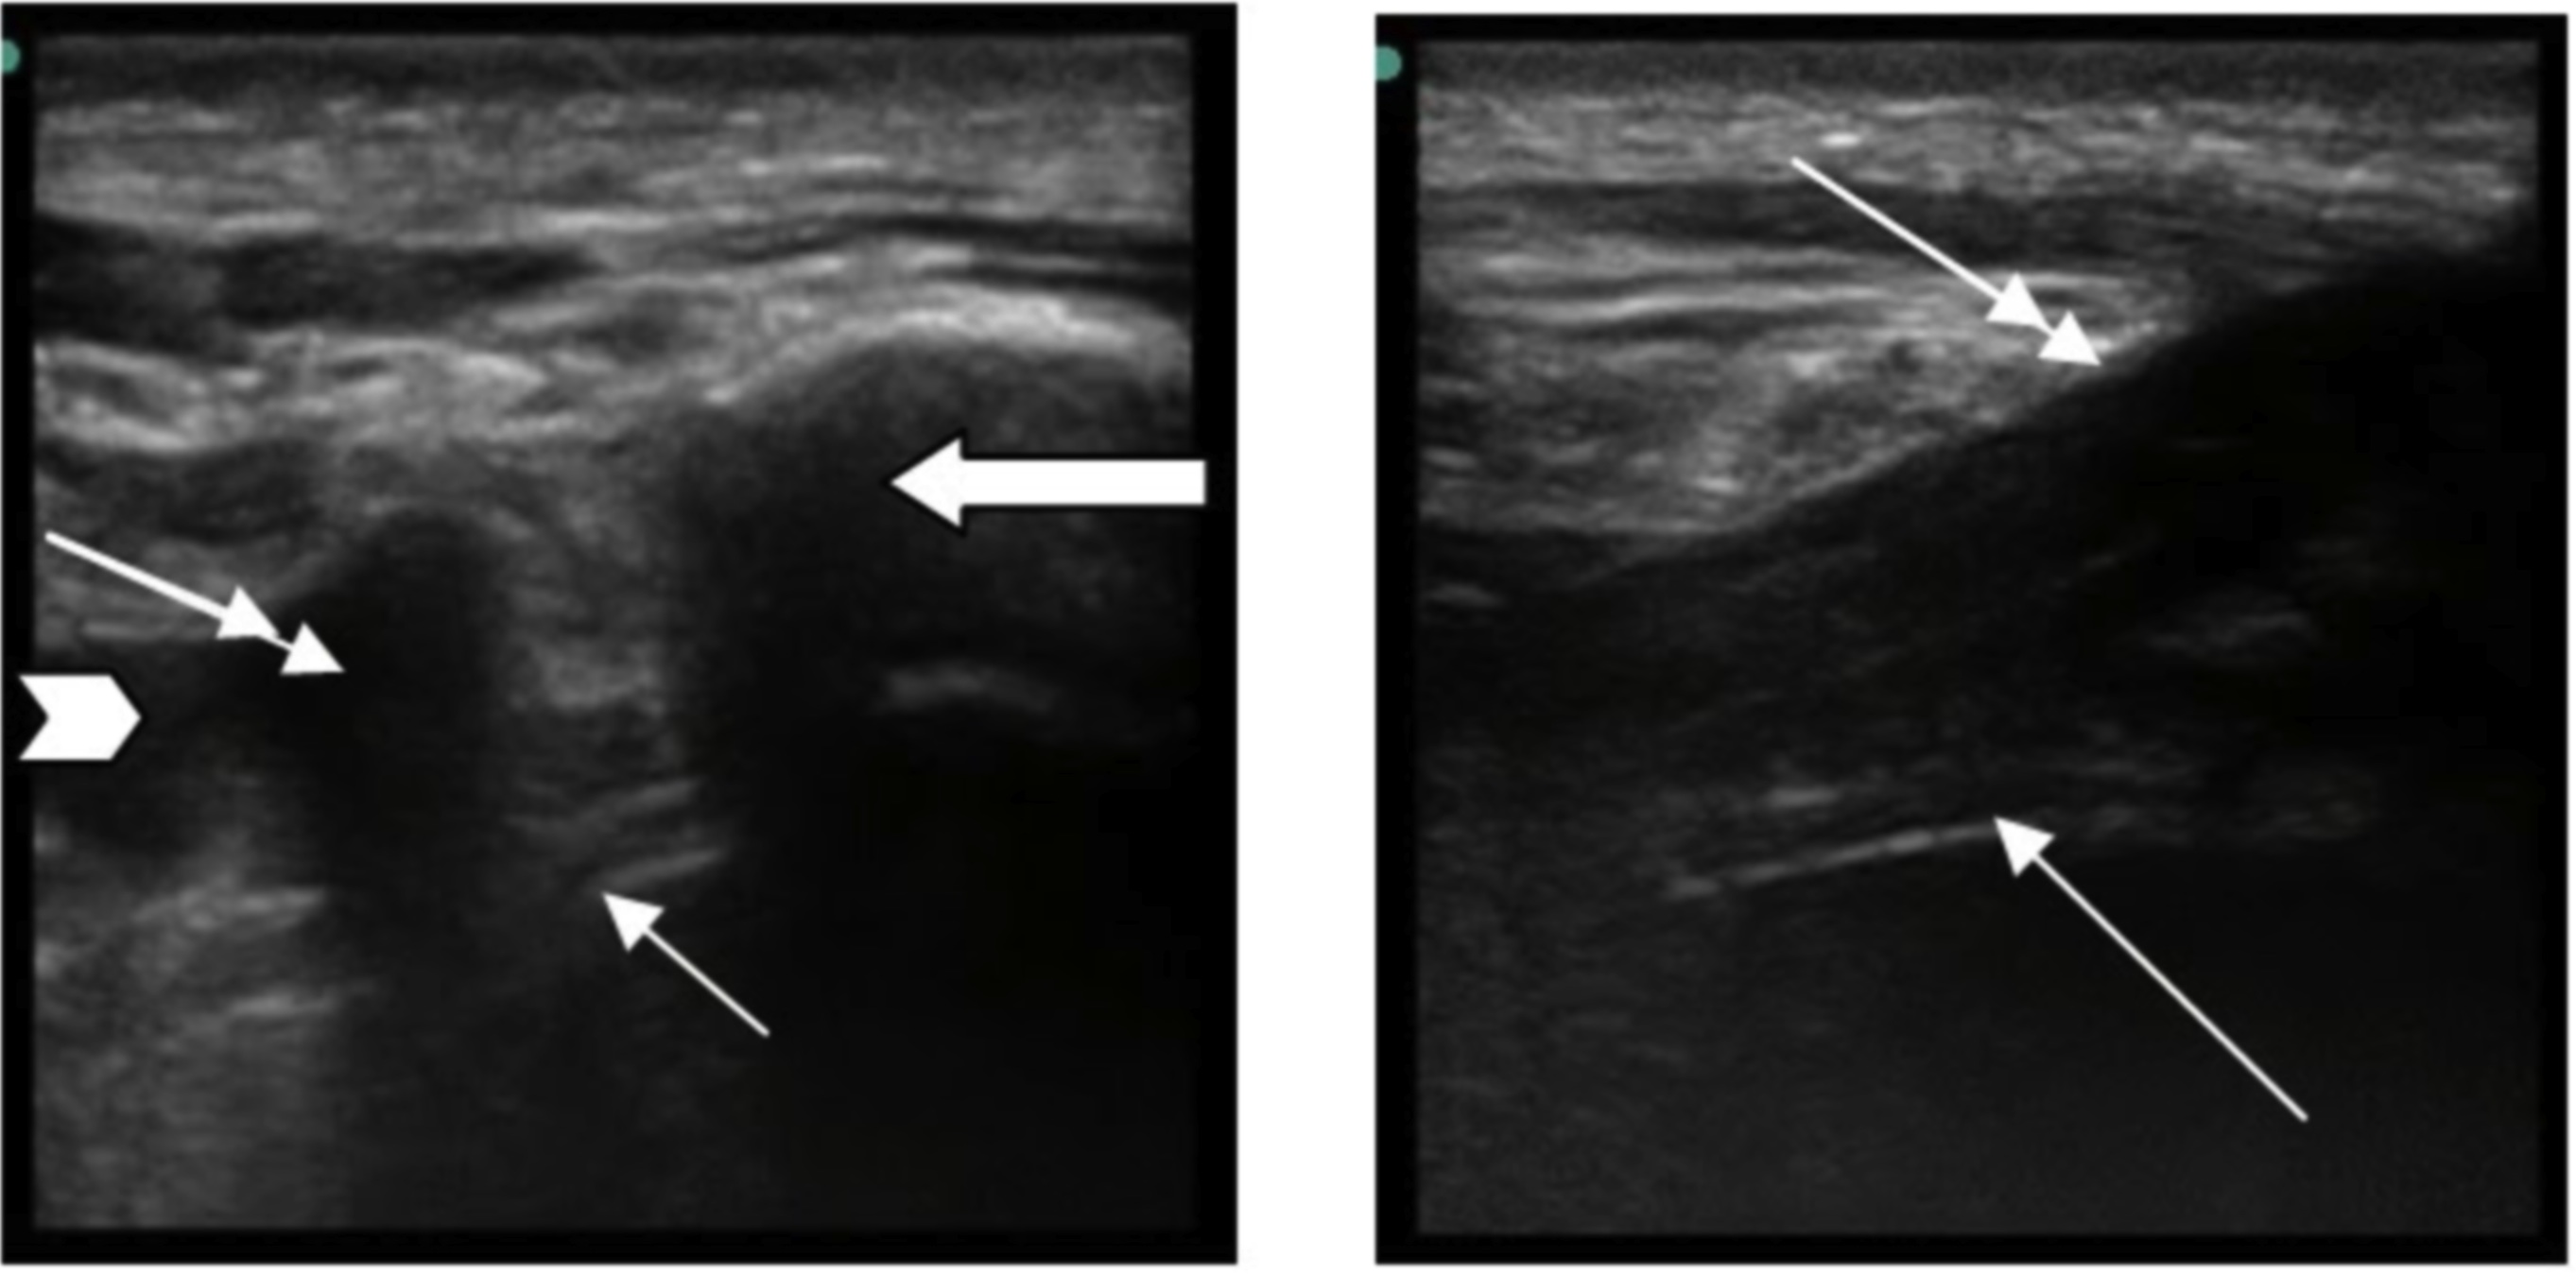

So, there are some parts of the chest missing (namely, the lower portion and costophrenic angles) on this not-so-great picture from my iPhone, but the trauma team and I did not appreciate a pneumothorax on this image. And, it just goes to show those darn studies were right, US is more sensitive than a CXR. The patient went to CT and the OR got ready for his tib/fib, but my astute resident said that we should place a chest tube prior to the intubation as this could go bad and get worse (hello tension!) after intubation – and that would be just poor form – so, our trauma colleagues agreed and in went the chest tube after return from CT, The tube, by the way, I also confirmed by US guidance for its intrathoracic placement (of course, this is a new thing and a CXR also confirmed it): the tube (double arrow) seen as the hyperechoic walled (bright) structure with shadow posteriorly next to the larger rib in the transverse view (image on your left) and you can see it enter the pleural cavity in the longitudinal view (image on your right): The landmark picture was not the actual victim, just a very nice medical student who allowed us to place the tough tape for the picture. Gotta love them! Pretty cool stuff, I tell ya!!